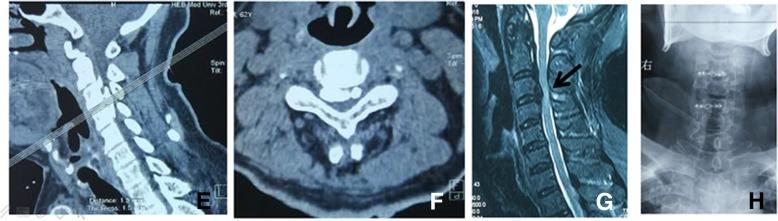

Analyses of effect factors associated with the postoperative dissatisfaction of patients undergoing open-door laminoplasty for cervical OPLL: a retrospective cohort study.

This study aimed to investigate the effect factors associated with the postoperative dissatisfaction of patients undergoing open-door laminoplasty for cervical OPLL.

In this study, 194 patients, who underwent open-door laminoplasty for cervical OPLL from January 2009 to January 2016, were retrospectively reviewed. The Patient Satisfaction Index (PSI) was collected at discharge, 6 months, 1 year, and the last follow-up. According to the PSI, patients were divided into satisfied group and dissatisfied group. The possible effect factors included demographic variables and surgery-related variables.